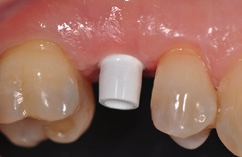

Die Implantate wurden im Anschluss mit einer ausreichenden Primärstabilität von 30 Ncm und einem suprakrestalen Anteil 0,6 mm platziert. Diese suprakrestale Positionierung wird durch einen gegebenenfalls am Profilbohrer anbringbaren Tiefenstopp (Abb. 7) vereinfacht. Für das Einbringen der Implantate steht ein neues, zur „Inter-X“-Innenverbindung formschlüssiges Eindrehinstrument (Abb. 8) zu Verfügung, wodurch eine optimale Kraftübertragung während des Inserierens des Implantats gewährleistet wird (Abb. 9). Die Einheilkappen sind deutlich abgeflacht und ermöglichen einen einfachen primären Wundverschluss (Abb. 10 und 11). Im vorliegenden Fall verlief die Wundheilung komplikationslos. Nach einer auch für Keramikimplantate heute üblichen Einheilungszeit von 3 Monaten zeigten sich die Implantate in der Röntgenkontrollaufnahme stabil osseointegriert (Abb. 12). Es fanden sich an beiden Implantat-Loci entzündungsfreie Weichgewebsverhältnisse, woraufhin mit der prothetischen Versorgung des Implantats begonnen werden konnte.

Für den Reentry wurde für das Einbringen des Gingivaformers eine minimale krestale Inzision angelegt (Abb. 13). Nach Abheilung der Weichgewebe (Abb. 14) konnte 2 Wochen später mit Reposition des Abformpfostens geschlossen abgeformt (Abb. 15) und das Meistermodel erstellt werden Da es sich um ein 2-teiliges Implantatsystem handelt und die Abutments ebenfalls aus hochfester ATZ-Keramik bestehen, lassen sich diese – falls nötig – entweder in der Praxis oder im Dentallabor durch Beschleifen individualisieren (Abb. 16). Für NobelPearl stehen sowohl gerade als auch 15° abgewinkelte Abutments mit 1 mm und 3 mm Gingivahöhe zu Verfügung. Im CAD/CAMVerfahren wurde eine monolithische Zirkonkrone aus Zolid FX (Amman Girrbach) mit okklusalem Zugang zum Schraubenkanal gefertigt (Dentallabor Studio für Zahntechnik, Dirk Tartsch).